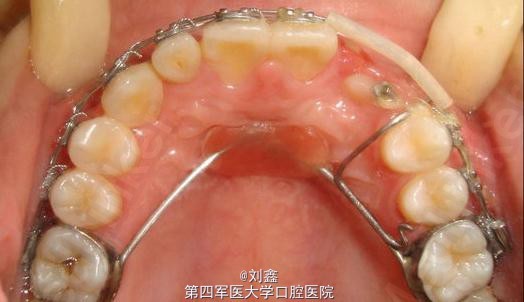

患者女 17岁 主诉:上尖牙未萌出及上前牙折断求矫治

1.右上乳尖牙滞留,右上尖牙近中阻生。 2.右上侧切牙冠折。 3.左上尖牙反合及上前牙不齐。

牵引埋伏13,预留12间隙待矫治结束后行桩核冠修复。 矫治步骤: 1.直丝弓矫正器排挤上颌牙。 2.改良上颌Nance托加强上后牙支抗及牵引埋伏13。 3.改良Hawlays式保持器保持。 4.12固定修复

13埋伏于12与11之间,在牵引13时需注意其牵引的方向。